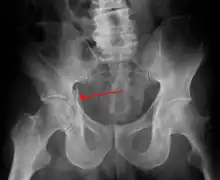

Fractures of the acetabulum occur when the head of the femur is driven into the pelvis. This injury is caused by a blow to either the side or front of the knee and often occurs as a dashboard injury accompanied by a fracture of the femur.[1]

Fracture of the acetabulum